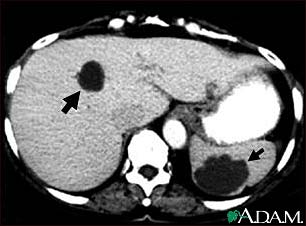

Polycystic kidney disease (PKD) is a kidney disorder passed down through families. In this disease, many cysts form in the kidneys, causing them to become enlarged.

People with PKD have many clusters of cysts in the kidneys. What exactly triggers the cysts to form is unknown.

- Cysts in the liver, pancreas, and testes

As many as half of people with PKD have cysts in the liver.

PKD and cysts on the liver or other organs may be found using the following tests: